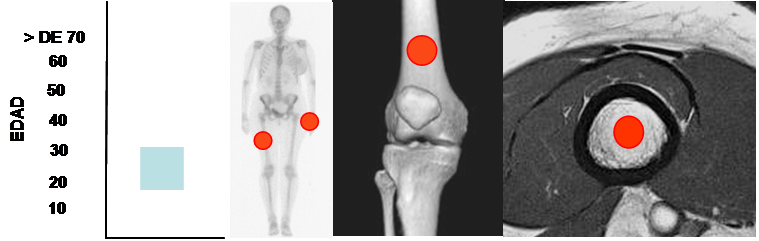

Frecuente entre la 3º y 4º décadas, en huesos tubulares (Fémur) y los huesos cortos de las manos. (21). (Fig 85).

Fig 85. Encondroma.

Mayor frecuencia entre la 3º y 4º décadas. Predominio en el fémur y las manos.

Lesión diafisiaria, de ubicación central.